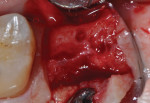

The patients were referred for the placement of dental implants to a clinical private practice limited to periodontics and dental implants. Informed consent was obtained prior to treatment. Anesthesia was obtained with local infiltration using articaine 4% with 1:100,000 epinephrine, except in those patients where this could not be tolerated and carbocaine 2% with 1:20,000 levonordefrin was used. Sulcular incisions were performed around the tooth to be extracted and were minimally extended to the adjacent teeth to mobilize the flap. Teeth were extracted using elevators and extraction forceps. In situations that were more challenging, a piezoelectric handpiece (Piezotome 2™, ACTEON North America, www.acteongroup.com) or dental high-speed handpiece were used to free up the root that was in the socket. Upon the tooth’s removal, the socket was curetted thoroughly to remove any residual soft tissue, and the socket was inspected to see whether it was intact (Figure 1). If the buccal or lingual plates were lost in any way, the flap was extended to provide better access to and visualization of these areas. The sockets were irrigated with povidone iodine for approximately 1 minute to further reduce any residual bacterial contamination of the site and then rinsed of this agent by copious use of sterile water.